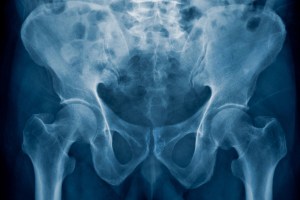

What makes us human? It’s all in the hips

Study shows how pelvis takes shape and what genes orchestrate the process.